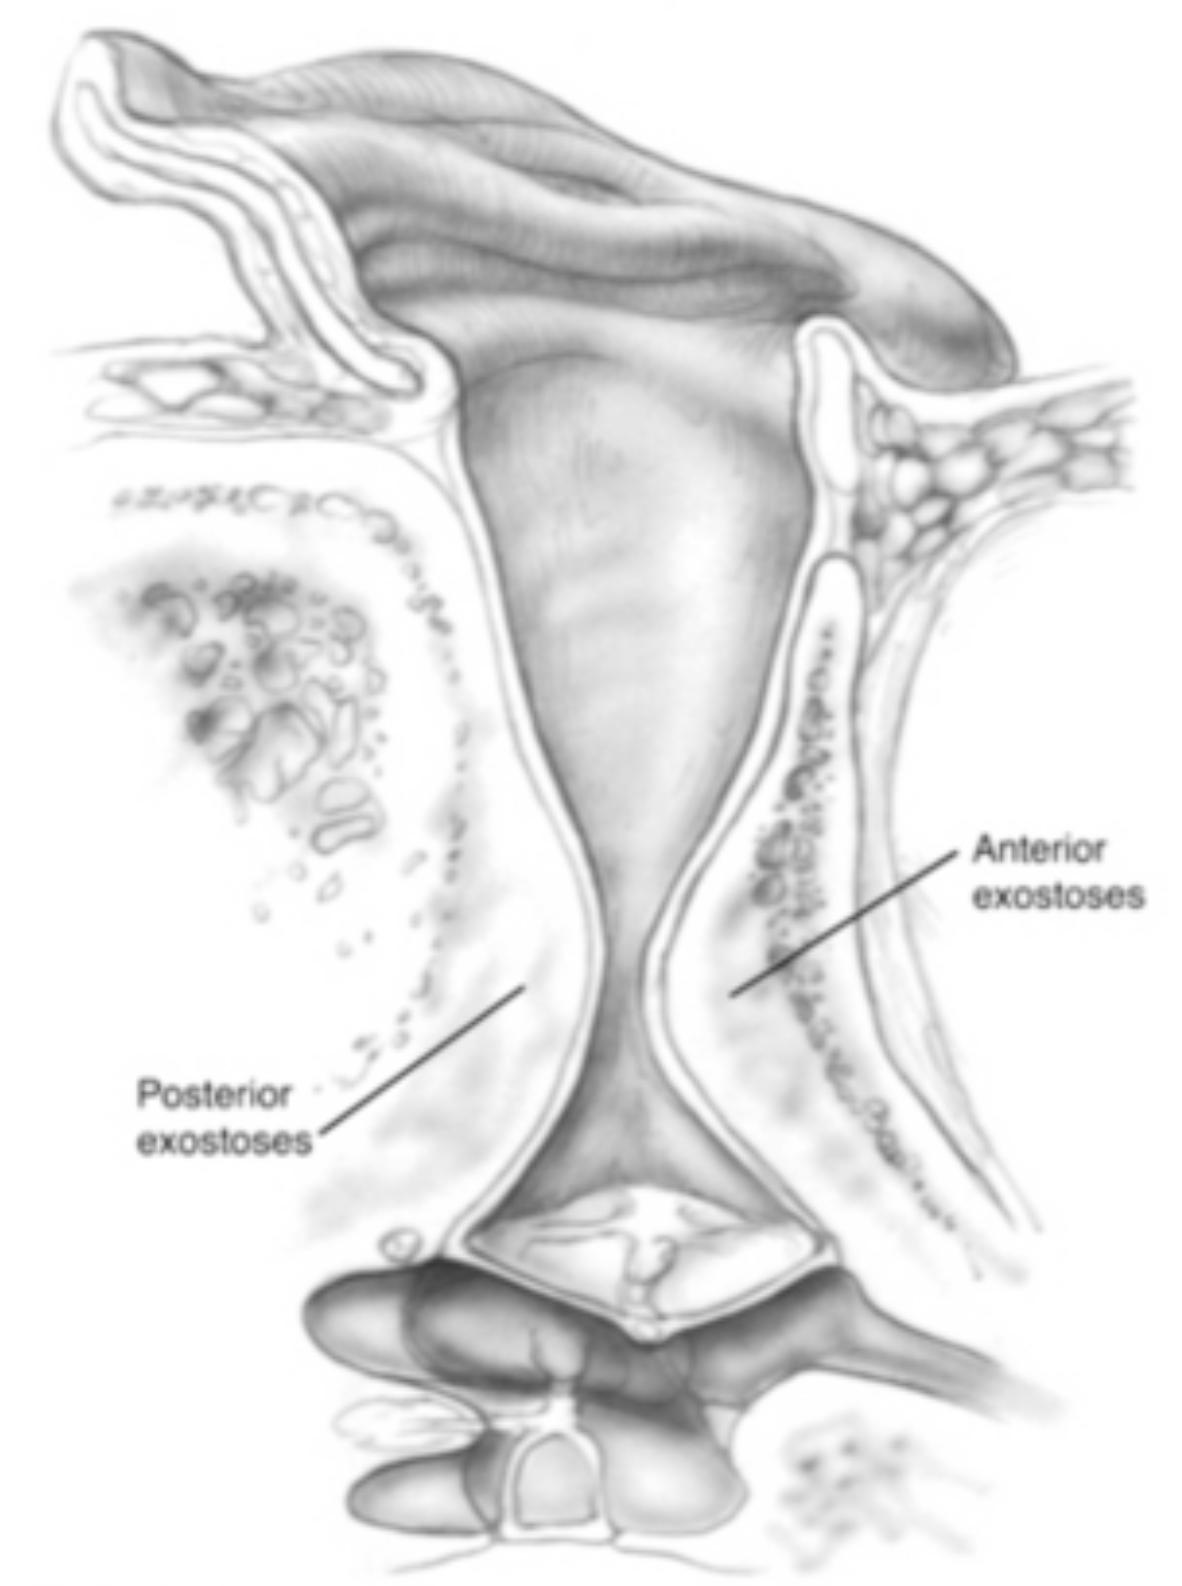

Advanced otology encompasses complex ear and skull base conditions requiring specialized surgical care. We offer cochlear implants and bone conduction implants for hearing loss, treat acoustic neuroma and temporal bone tumors, and perform stapes surgery for otosclerosis. Our team also manages cholesteatoma, superior canal dehiscence, and other advanced ear conditions. Select a topic below to learn more.